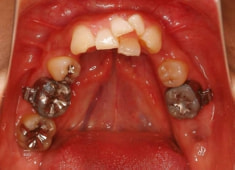

治療前

治療開始時